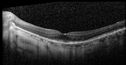

77 year old female Blurred Vision OU. Severity: worsening. Context Onset/Aggravation: comes and goes. Quality: distorted "wavy lines" while watching TV. Duration of Problem: many years, since 2017. Modifying Factors: worse in bright light. Associated Symptoms: longstanding floaters OU, intermittent. Associated Symptoms: no flashes. The patient was on elmifor her chronic cystitis but stopped it 2 years ago. Medical Hx: Bladder cystitis. Influenza Immunization Received. Pneumococcal Vaccine Received. Asthma. Dysmetria. Surgical Hx: cataract surgery OU. Left shoulder replaced. Back Surgery. AVM brain surgery. Systemic Meds: Synthroid 112 MCG Oral Tablet qam. Lamictal 300 MG Oral Tablet qam. Lamictal 150 MG Oral Tablet qhs. Cymbalta 60 MG (duloxetine hydrochloride 67.3 MG) Enteric Coated Capsule. Wellbutrin 00 MG Oral Tablet qam. Wellbutrin 300 MG Oral Tablet qhs. Ativan 2 MG Oral Tablet 1 tablet qhs. atorvastatin (as atorvastatin calcium) 20 MG Oral Tablet qam. Singulair 10 MG Oral Tablet qam. Abilify 15 MG Oral Tablet qhs. ropinirole 0.50 MG (as ropinirole hydrochloride) Oral Tablet qhs. pantoprazole 10 MG (as pantoprazole sodium sesquihydrate 22.56 MG) Delayed Release Oral Tablet qam. Albuterol Sulfate 90 mcg prn. Meloxicam 15 MILLIGRAM In 1 TABLET ORAL TABLET prn. Zofran 4 MG Oral Tablet 1 tablet prn. Fish Oil. Colace. Omega 3. Calcium Carbonate. VA OD: Dcc20/63 OS: Dcc20/32 IOP: TP: OD:12 OS:14 She had been on elmiron for 20 years and has been progressing since stopping the medication.

Elmiron (pentasosan polysulfate) Macular Toxicity105 views77 year old female who had been on Elmiron for 20 years and stopped it 2 years ago